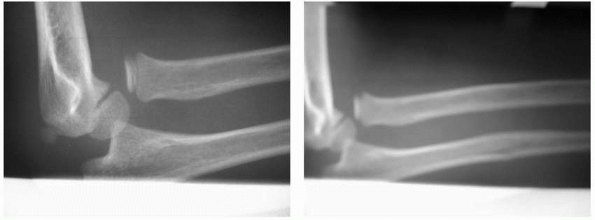

![]() |

FIGURE 12-11 The AP view (A) demonstrates an apparently located radial head, but the lateral view (B) shows an anterior dislocation of the radial head. Note the disruption of the radiocapitellar line.